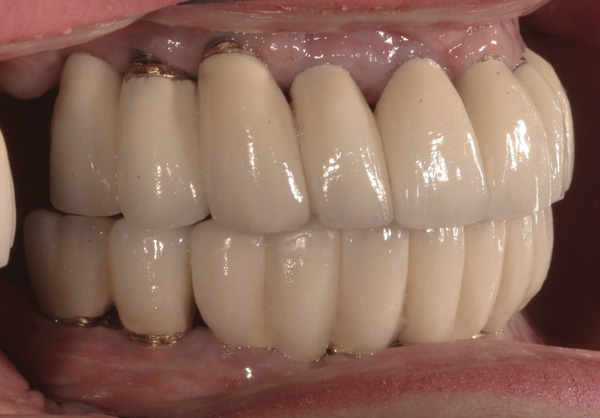

Background: This patient had a failing maxillary dentition and refused to wear a removable prosthesis. A staged approach was employed to retain some of his natural tooth abutments, and recession was noticed at the time of the impression for the second group of implants. Figure 1 shows the patient following insertion of the first set of implant custom abutments; the adjacent natural teeth are still present to support the provisional bridge. Seven months later, as shown in Figure 2, those first-stage custom abutments exhibited evidence of 1 mm to 3 mm of recession.

Figure 1 Patient following insertion of first set of implant custom abutments.

Figure 1

Figure 2 After 7 months, the first-stage custom abutments exhibited evidence of 1 mm to 3 mm of recession.

Figure 2